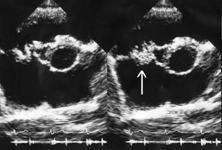

5. Вегетации на клапанах по данным ЭхоКГ